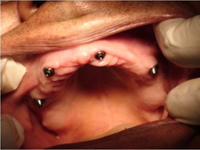

Během let může postupnou ztrátou zubů zůstat v ústech omezený počet zubů, které umožňují držení zubních náhrad.

V důsledku přetížení zbylých zubů např. houpavými pohyb snímacích náhrad dochází k uvolnění těchto zubů a držení můstků a protéz je tak velmi těžké. V těchto případech můžeme pomocí implantátů zvýšit počet pilířů a tím zabránit přetěžování a ztrátě zbylých zubů